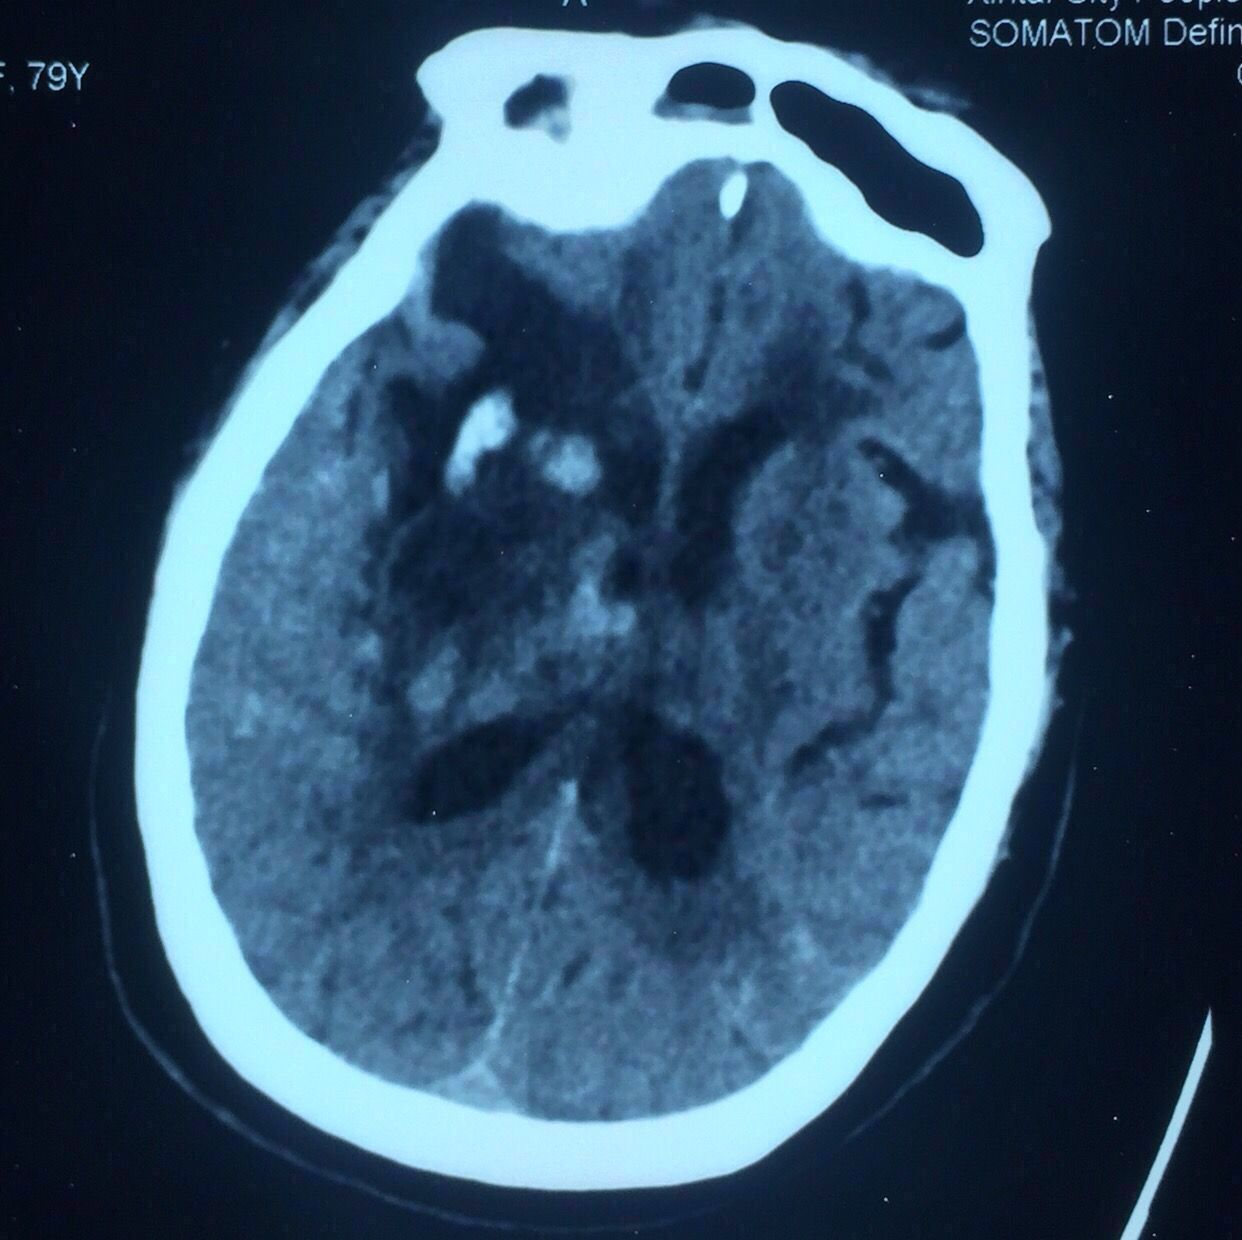

术后第7天复查,见上图,血肿引流比较充分。

患者仍昏迷状态,肺部感染较重,家属最终放弃气管切开手术放弃进一步治疗,出院回家。